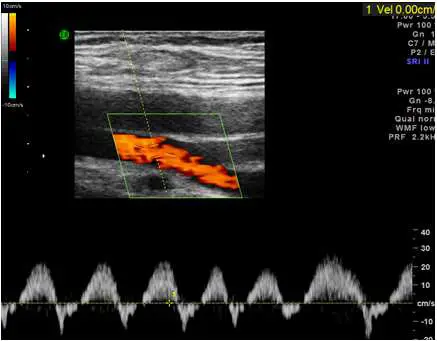

85 歲男性病人,下肢腫脹。下圖為左側腹股溝血管掃描,則下列選項何者正確?

本圖為左側腹股溝區彩色都卜勒超音波(duplex ultrasound):

彩色都卜勒影像(上半部):

- 血管呈現橙紅色單一方向彩色血流訊號,顏色均勻、無彩色鑲嵌(mosaic pattern)

- 無高速渦流或混色現象,排除動靜脈廔管

頻譜都卜勒(下半部):

- 波形為單一方向(antegrade)、連續性、隨呼吸週期規律起伏

- 波形基線附近輕微波動,符合典型「呼吸相位性(respiratory phasicity)」

- 無高速三相波形(triphasic waveform),無反向血流成分

- 低速、平緩的波形形態 → 典型正常靜脈頻譜

此頻譜波形與正常股靜脈(femoral vein)的特徵完全吻合:自發性(spontaneous)、前向性(antegrade)、呼吸相位性(phasic with respiration)。

(A) 此頻譜代表所掃描為正常股動脈 ❌ 錯誤。正常股動脈(femoral artery)應顯示三相波形(triphasic waveform)